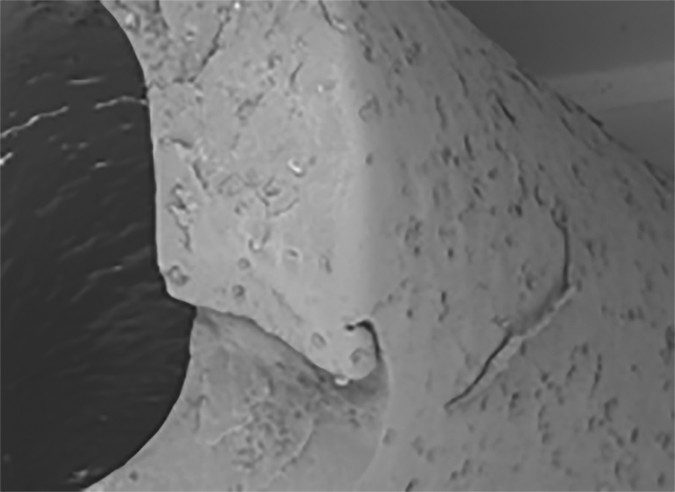

B, Magnification of rupture site (×232) shows additional surface defect in close proximity to rupture site.

Braun et al. [4] performed a set of experiments investigating the mechanical properties of both de novo and explanted port catheters. They found clear correlation between material properties and clinical performance. Specifically, both native catheters exposed to moderate mechanical stress tests and explanted catheters from cancer patients had a progressive loss of barium sul-fate (BaSO4) particles, which are introduced in almost every catheter material to make it radiopaque. The loss of BaSO4 particles between the silicon bonds essentially leaves microscopic holes in the catheter, leaving areas of increased vulnerability that render the catheter prone to rupture (Fig. 1). Interestingly, more BaSO4-related cracks were observed in silicone than in polyurethane catheters.